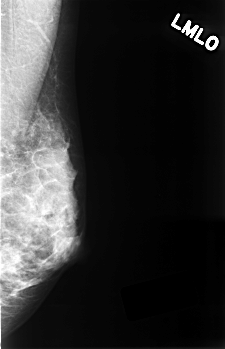

C_0336_1.LEFT_MLO

C_0336_1.LEFT_CC

LEFT_MLO LINES 4528 PIXELS_PER_LINE 2920 BITS_PER_PIXEL 12 RESOLUTION 50 NON_OVERLAY